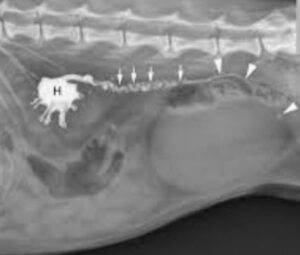

↑ 上の写真は、腎結石から尿管結石が連なっている症例のレントゲン写真です。

◆ 左の大きな白い部分が、腎結石です。

◆ 腎臓の右に続く線状の白い部分は、尿路結石です。